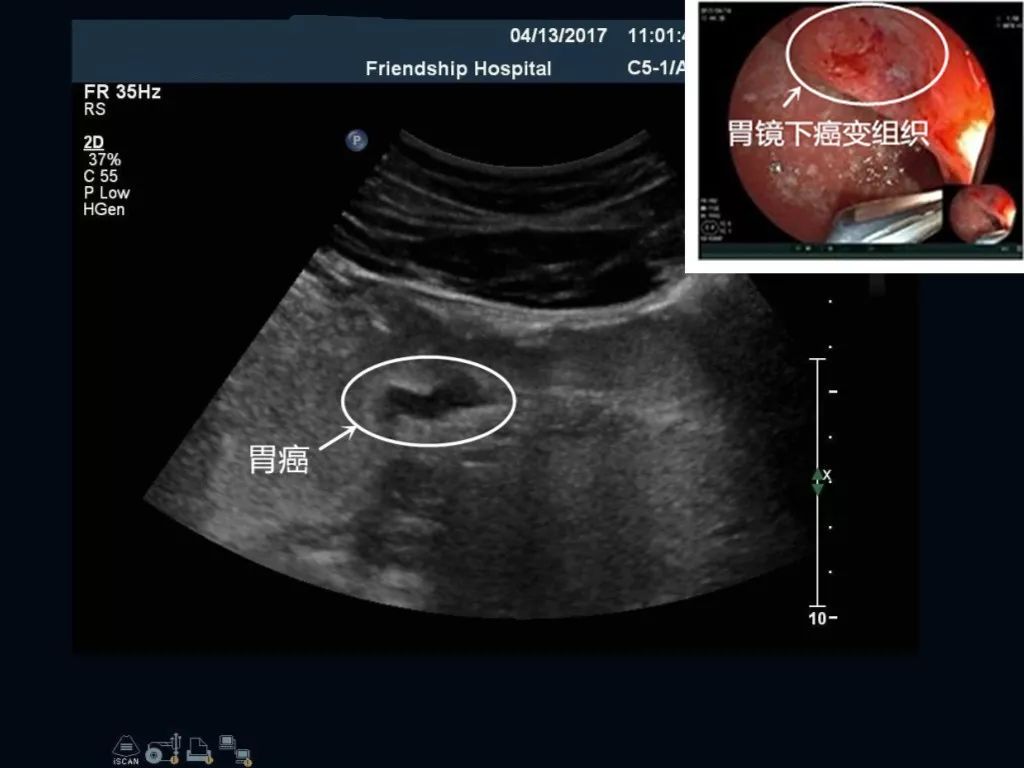

胃角部胃癌: